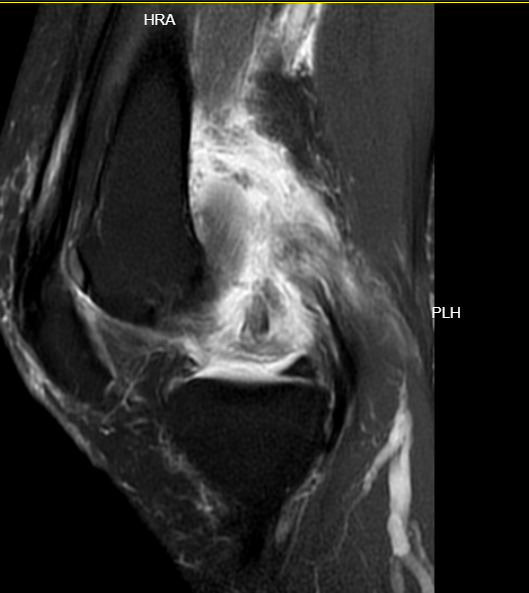

MR检查可见膝关节脱位、前后交叉韧带断裂、内侧副韧带断裂并卡关节内(导致关节无法复位)